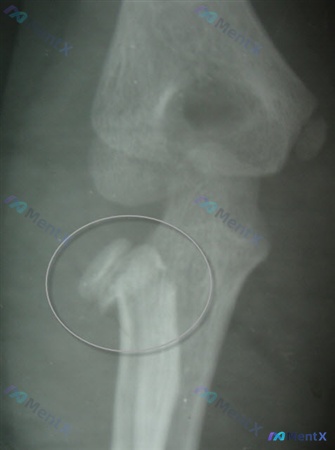

整理到一张肘关节斜位透视的影像资料,先放客观观察到的点,大家第一眼会怎么定性? 1. 骨性结构:肱骨远端、尺骨近端、桡骨近端整体轮廓完整,但桡骨头/颈部区域可见骨皮质中断 2. 高密度影:桡骨颈处有一枚清晰的金属高密度影,呈横向走行 3. 关节与软组织:肱桡、肱尺关节间隙看起来尚可,周围软组织轮廓平...

整理到一份影像资料,大家帮忙看看: 基本情况:受检者左侧前臂斜位X光片,图像显示为左侧前臂斜位投照,可见尺骨与桡骨部分重叠;曝光度尚可,骨小梁结构可见,视野主要集中在肘关节及前臂近段。 影像核心表现: - 骨骼:左侧桡骨近端(骨颈/干骺端区域)可见骨皮质不连续,骨折线向内侧成角,桡骨头与骨干解剖轴线...

整理到一个12岁男性的肘部创伤病例: - 8英尺跌落,手掌撑地受伤 - 急诊X光显示桡骨颈移位 - 镇静下行闭合复位,复查X光(正位)显示:桡骨头/颈仍有明显骨质连续性中断,碎裂/多块骨碎片,移位分离,台阶感明显,肱桡关节解剖异常,局部软组织肿胀 目前的问题是:下一步最合适的治疗是什么?